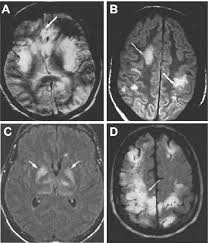

Rasmussen's encephalitis is a progressive hemispheric atrophy of unknown origin. Hsv1 encephalitis should always be considered on initial mri. Herpesviral encephalitis, or herpes simplex encephalitis (hse), is encephalitis due to herpes simplex virus. Multiple subtypes of the herpes virus family are neurotropic and may cause devastating neurologic injury. Herpes simplex (hsv) encephalitis is the most common cause of fatal sporadic fulminant necrotizing viral encephalitis and has characteristic imaging findings. The differential diagnoses include limbic encephalitis (paraneoplastic), gliomatosis cerebri, and status epilepticus. In some cases, advanced imaging techniques such as computed tomography and magnetic resonance imaging (mri) can maertzdorf j, et al. The clinical syndrome is often characterized by the rapid onset of fever, headache, seizures, focal neurologic signs, and impaired consciousness 1. The images show symmetrical bilateral putaminal vasogenic oedema with mild restriction on diffusion and no bleed. The mortality from hsv is high, so commencement of treatment with antiviral drugs (acyclovir) is recommended without delay with the typical radiological find. Herpes simplex encephalitis is a type of infectious encephalitis which happens when herpes simplex virus (hsv) enters the brain. Results in brain necrosis and liquefaction. Severe infection, particularly untreated herpes simplex virus (hsv) encephalitis, can cause brain hemorrhagic necrosis.

Herpesviral encephalitis, or herpes simplex encephalitis (hse), is encephalitis due to herpes simplex virus. The differential diagnoses include limbic encephalitis (paraneoplastic), gliomatosis cerebri, and status epilepticus. Typical mri features of herpes simplex encephalitis. Herpes simplex encephalitis is a type of infectious encephalitis which happens when herpes simplex virus (hsv) enters the brain. Contributed by mark cohen, m.d. But changes are not specific for hsv (e.g. The mortality from hsv is high, so commencement of treatment with antiviral drugs (acyclovir) is recommended without delay with the typical radiological find. Severe infection, particularly untreated herpes simplex virus (hsv) encephalitis, can cause brain hemorrhagic necrosis.

Herpes simplex encephalitis is a type of infectious encephalitis which happens when herpes simplex virus (hsv) enters the brain. The mortality from hsv is high, so commencement of treatment with antiviral drugs (acyclovir) is recommended without delay with the typical radiological find. Hsv encephalitis causes inflammation, hemorrhage and edema. Typical mri features of herpes simplex encephalitis. Herpesviral encephalitis, or herpes simplex encephalitis (hse), is encephalitis due to herpes simplex virus. Brain ct scan must be urgently performed to rule out a brain lesion with mass effect that would contraindicate lumbar puncture. In some cases, advanced imaging techniques such as computed tomography and magnetic resonance imaging (mri) can maertzdorf j, et al. Multiple subtypes of the herpes virus family are neurotropic and may cause devastating neurologic injury.

Mushroom sign of pyloric stenosis. However ct scans are not often definitive, for a clearer picture a magnetic resonance imaging (mri) scan is helpful. In some cases, advanced imaging techniques such as computed tomography and magnetic resonance imaging (mri) can maertzdorf j, et al. What the radiologist can expect to see prenatally and postnatally. Hsv encephalitis causes inflammation, hemorrhage and edema. Severe infection, particularly untreated herpes simplex virus (hsv) encephalitis, can cause brain hemorrhagic necrosis. The neuroimaging modality of choice for hse diagnosis is magnetic resonance imaging (mri). The images show symmetrical bilateral putaminal vasogenic oedema with mild restriction on diffusion and no bleed. But changes are not specific for hsv (e.g. Mri is the preferred imaging modality for hsv encephalitis. The above described radiological findings are impressive of herpes simplex encephalitis. Hsv1 encephalitis should always be considered on initial mri. Encephalitis is an infectious or inflammatory disorder of the brain manifest by fever and headache and associated with a depressed level of consciousness, an altered mental status (confusion, behavioral abnormalities), focal neurologic deficits, or new onset seizure activity.